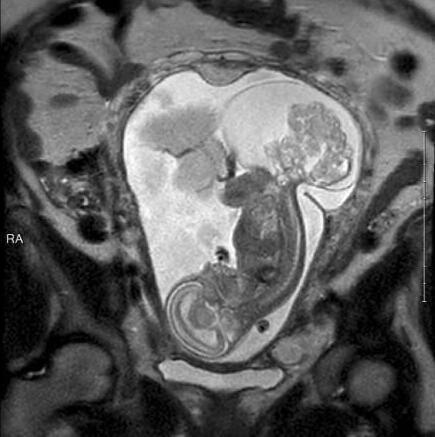

今年6月,琳莉23周零5天的時候,瑪格麗特在德克薩斯兒童醫(yī)院接受了手術,這個時候的腫瘤都快比琳莉大了。手術共進行了5個小時。“摘除腫瘤時我們做得很快,只花了20分鐘。最花時間的是打開子宮。我們不想讓媽媽的健康受到影響,所以進行得很仔細。”

由于腫瘤已經(jīng)很大,要取出來的話還是需要切口,所以摘除腫瘤時胎兒完全離開了瑪格麗特的子宮,暴露在空氣中。“所有的羊水也出來了,非常神奇。”卡斯醫(yī)生說。手術中,琳莉的心臟僅保持低頻跳動,都快停止了。卡斯邀請了心臟專家協(xié)助手術。心臟專家保持琳莉的心臟處于可接受的狀態(tài),以保證手術的順利進行。

醫(yī)生們摘除了大部分腫瘤。手術結束后,醫(yī)生把琳莉放回了媽媽的子宮內(nèi),然后縫合了子宮。“我們打開子宮再縫上它,這個嘗試居然成功了,這簡直就是個奇跡。”卡斯醫(yī)生激動地說。手術結束后,瑪格麗特需要一直躺在床上休息,直到妊娠期結束。接下來的12周里,瑪格麗特一邊忍受疼痛,一邊期待琳莉的出生。